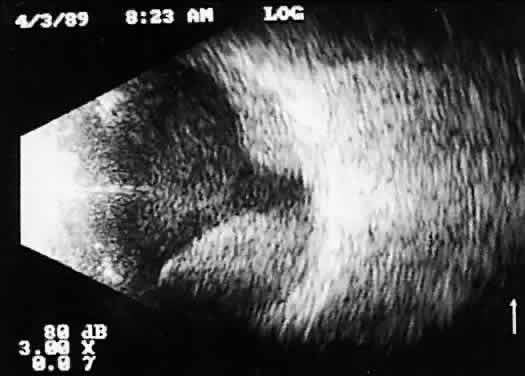

Recent improvements in image quality and fused, real-time display have made ultrasound image interpretation easier for every ultrasonographer. Visualization of subtle changes such as movement and recognition of the posterior formed vitreous hyaloid are now possible, even in clear media situations. These clear vitreous structures, which are often exceedingly difficult to appreciate optically, can be recognized ultrasonically after a relatively short period of training (Fig. 17). Clinically, establishing the position of the posterior hyaloid is important in evaluating a variety of vitreous retinal disorders, such as macular holes, tractional detachments, and partial or complete vitreous separations.16,17

Fig. 17. Contact B-scan: posterior formed vitreous face separation, with prominent Weiss ring evident.